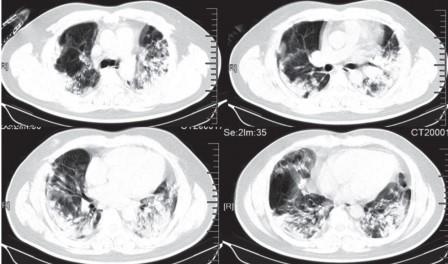

Tomografía muestra daño pulmonar en paciente de 44 años al día 15 de los síntomas. The Lancet

Una revisión de los escáneres pulmonares de nueve pacientes infectados en Princess Margaret encontró patrones similares al vidrio esmerilado en todos ellos, lo que sugiere que hubo daño en los órganos.